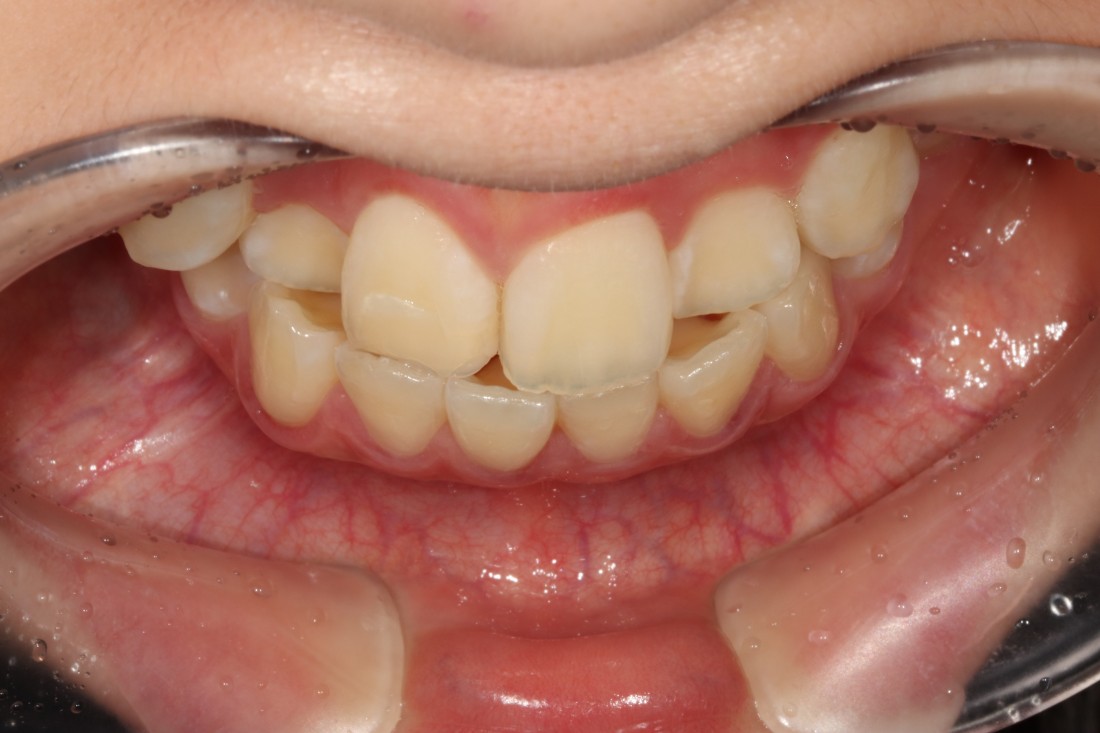

수완동 치아교정 기간은

치아의 이동속도에 따라

예상기간보다 짧아질 수도,

혹은 길어질 수도 있는데요.